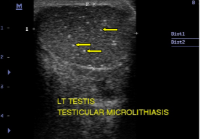

Testicular Microlithiasis: How Concerned Should We Be?

Dr Okere PCN., N. Ani, NI Iloanusi, DU Itanyi, IJ Okoye, D. B. Olusina (Author)

10-15

Views | PDF/EPUB Downloads : 231 / 24

DOI: https://doi.org/10.82235/wajr.vol18no1.219